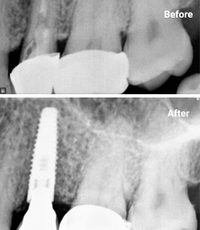

Single Tooth Implant

Single tooth implants replace a missing tooth without impacting neighboring teeth. This highly predictable solution acts like a natural root, supporting a crown while preserving the surrounding bone structure and teeth integrity.